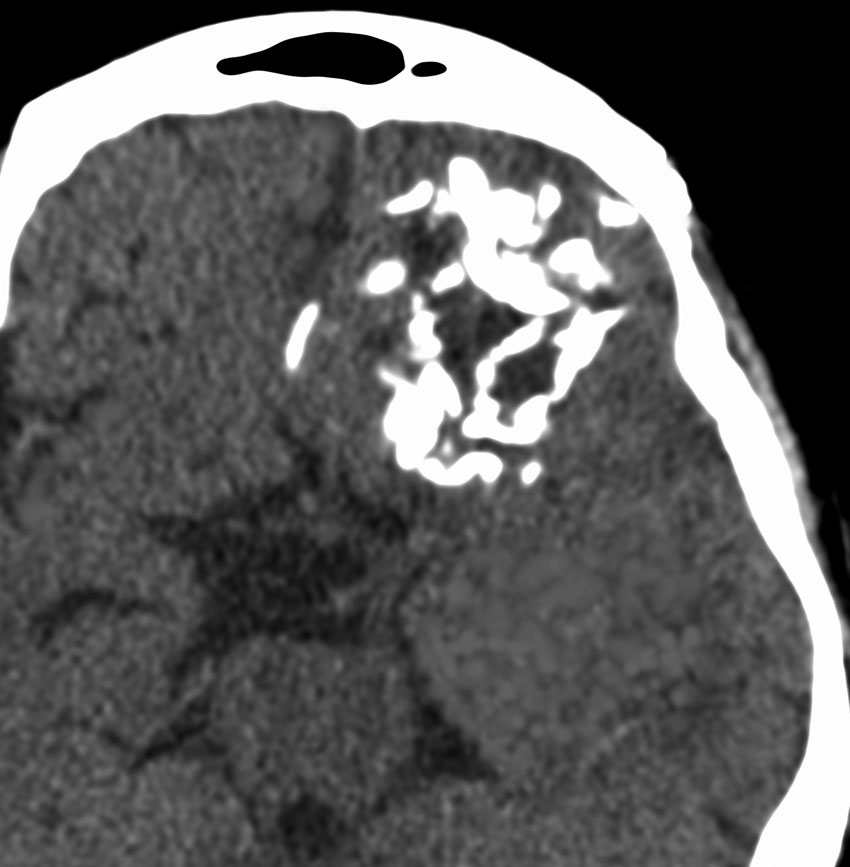

何と言っても診断的価値があるのは 石灰化 carcification です。左のCTの中央にみえる白い部分が石灰化です。この程度の石灰化でも診断的な価値があります。1p/19q codeletionがあるオリゴでした。病理では,均一な小型の円形核を有する細胞と多数の毛細血管 chickin-wire network がみられます。部分摘出後,放射線治療とテモゾロマイド化学療法でコントロールできています。

極めて高度な石灰化:脳石 brain stone

左は通常のCT,右は骨条件CTです。左前頭葉に巨大な石灰化を伴う乏突起膠腫があります。病理組織像は基本的にはグレード2です。石の塊のようにみえるので braine stoneと呼ばれ,CT eraでは oligodendrogliomaの hallmarkと言われました。